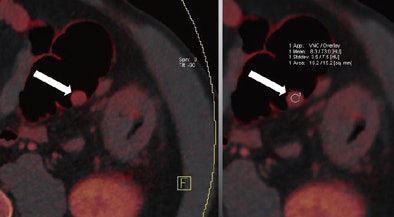

| Images are of a 65-year-old male patient who underwent a single acquisition at dual-source CTC. Above, a stenosing carcinoma was seen in the proximal sigmoid colon in 3D endoluminal views (left, middle) and 2D view (right). Below, an 18-mm colorectal adenoma was also found in the proximal sigmoid colon, and also appears to be enhancing. Bottom image shows an enhancing liver metastasis in the same patient. Virtual unenhanced (grayscale) images are created by electronically subtracting the contrast media. All images courtesy of Dr. Anno Graser. |

The technique can be used to determine the contrast media uptake of the polyp, as well as the baseline density of the lesion, directly measuring enhancement in HU and measuring the iodine in the lesion in grams per mL.